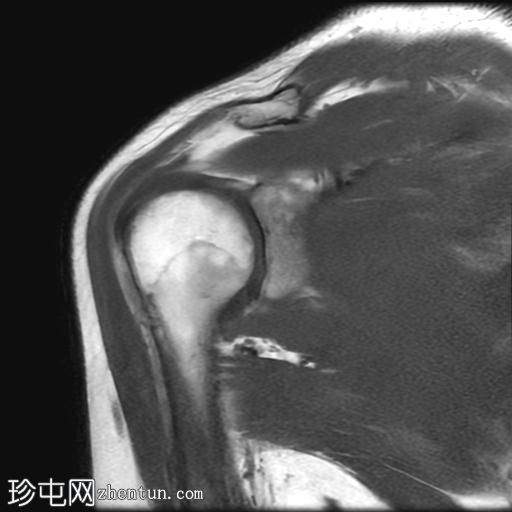

MRI

冠状位

T2加权像

T1加权像

冠状位PD加权像

脂肪抑制像

矢状位

PD加权像

肩袖钙化性肌腱炎:冈下肌腱上部纤维可见约7 x 14 mm的低信号病灶

冈上肌腱滑囊侧纤维可见轻度增高液体信号,提示肌腱病

肩峰II型

肩峰下滑囊可见轻度液体信号

肩袖钙化性肌腱炎是一种自限性疾病,由羟基磷灰石钙沉积引起,最常见于冈上肌腱。